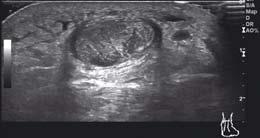

Staw skokowy dolny